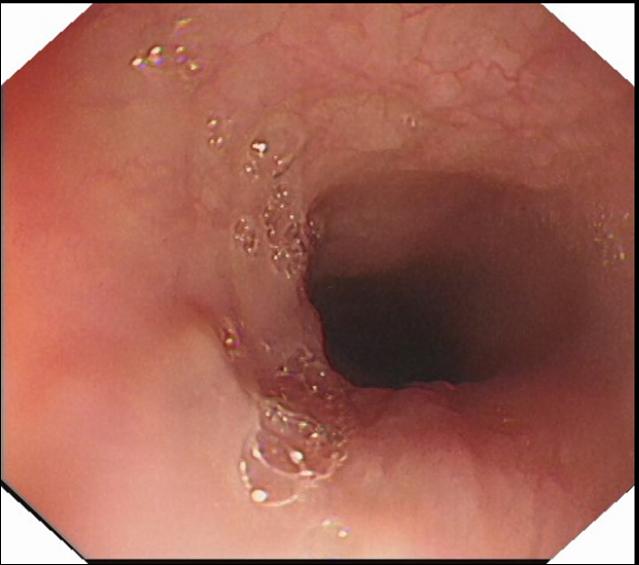

正常食管 食管静脉曲张TIPS术前 食管静脉曲张TIPS术后2年

科室开展消化道早癌诊断技术、高难度食管异物取出技术、食管胃镜静脉曲张内镜下治疗、内镜逆行胰胆管造影术(ERCP术)、消化道息肉切除术、胆胰管狭窄扩张及支架植入术、内痔治疗等。

食管胃底静脉曲张破裂出血 内镜下曲张静脉结扎术后EVL